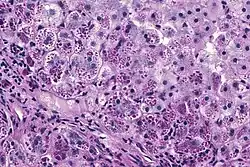

With A1AT deficiency, the pathogenesis of the lung disease is different from that of the liver disease, which is caused by the accumulation of abnormal A1AT proteins in the liver, resulting in liver damage.[9] As such, lung disease and liver disease of A1AT deficiency appear unrelated, and the presence of one does not appear to predict the presence of the other.[9] Between 10% and 15% of people with the PiZZ genotype will develop liver fibrosis or liver cirrhosis, because the A1AT is not secreted properly and therefore accumulates in the liver.[18] The mutant Z form of A1AT protein undergoes inefficient protein folding (a physical process where a protein chain achieves its final conformation). 85 percent of the mutant Z form are unable to be secreted and remain in the hepatocyte.[9] Nearly all liver disease caused by A1AT is due to the PiZZ genotype, although other genotypes involving different combinations of mutated alleles (compound heterozygotes) may also result in liver disease.[9] A liver biopsy in such cases will reveal PAS-positive, diastase-resistant inclusions within hepatocytes.[9] Unlike glycogen and other mucins which are diastase sensitive (i.e., diastase treatment disables PAS staining), A1AT deficient hepatocytes will stain with PAS even after diastase treatment - a state thus referred to as "diastase resistant". The accumulation of these inclusions or globules is the main cause of liver injury in A1AT deficiency. However, not all individuals with PiZZ genotype develop liver disease (incomplete penetrance), despite the presence of accumulated mutated protein in the liver.[9] Therefore, additional factors (environmental, genetic, etc.) likely influence whether liver disease develops.[9]

The gold standard of diagnosis for A1AD consists of blood tests to determine the phenotype of the AAT protein or genotype analysis of DNA.[9] Liver biopsy is the gold standard for determining the extent of hepatic fibrosis and assessing for the presence of cirrhosis.[9]